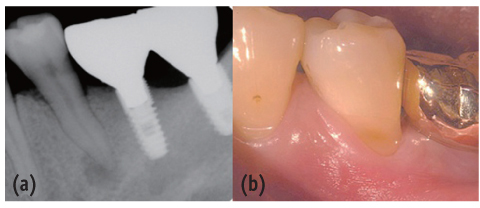

Figure 1

Preoperative periapical view and clinical photograph. (a) Periapical radiolucency on #35; (b) Cervical abrasion.

Figure 1 Preoperative periapical view and clinical photograph. (a) Periapical radiolucency on #35; (b) Cervical abrasion.